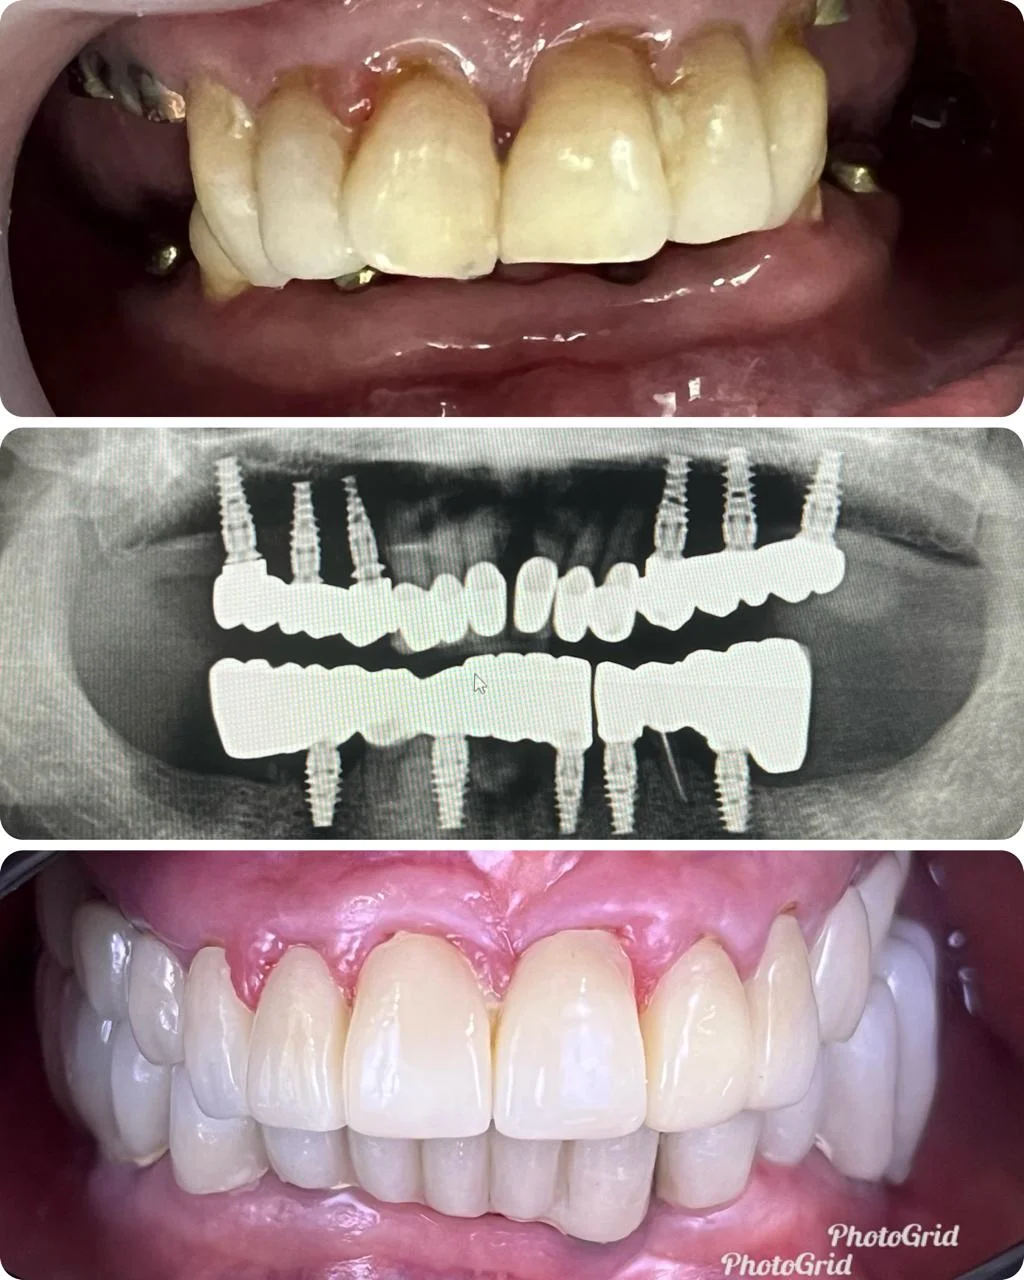

Showing Our Expertise In Dental Implantology